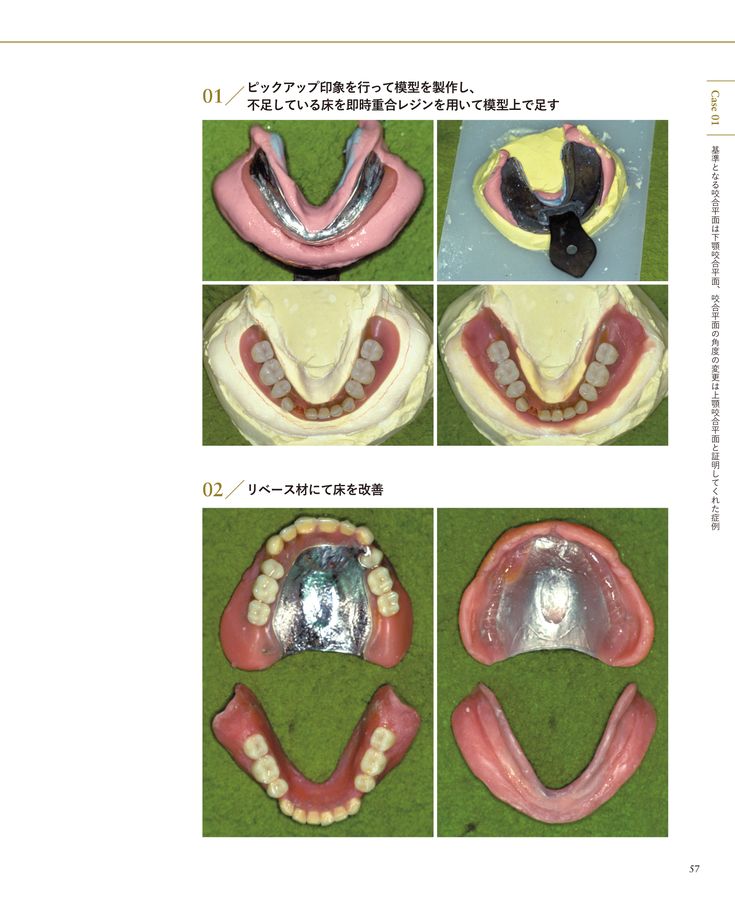

Amazon.co.jp: 義歯に血の通うまで アルプス歯科の総義歯製作。Amazon.co.jp: 義歯に血の通うまで アルプス歯科の総義歯製作。Amazon.co.jp: 義歯に血の通うまで : 中込敏夫, 向井道夫: 本。令和六年度 魚沼産コシヒカリ5キロと新潟県産コシヒカリ5キロ、計10キロ。株式会社 医療情報研究所 | 早くて簡単!総義歯吸着の神技。GPによる複製義歯を利用した総義歯製作 冨田 知孝先生。総義歯づくり すいすいマスター 総義歯患者の「何ともない」を。噛める、痛くない、審美的入れ歯で快適生活 「入れ歯110番。41dgXQG+tOL._BO30,255,255,。医学のあゆみ 289巻5号 MASLD/MASH ─研究と診療の最新情報 5月。総義歯の病理―基礎と臨床から導き出された総義歯製作法。学術04(最終回)「医科歯科介護」連携時代の保険で『噛める総。総義歯の病理―基礎と臨床から導き出された総義歯製作法。サンバレー書房カバーは若干スレあり中身は綺麗です定価20000円神経質な方はご遠慮ください#歯科医師#義歯#歯科技工士